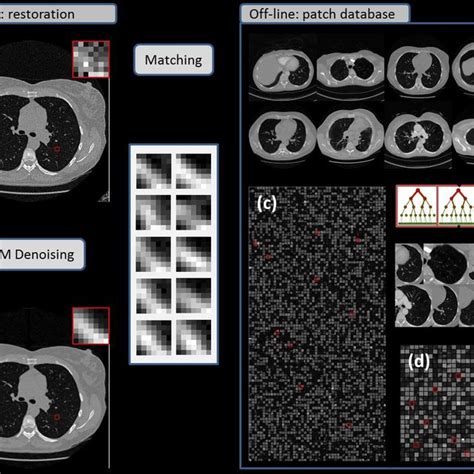

Explore this definitive medical imaging data reference, offering a clear and concise guide to the complexities of healthcare imaging data. This invaluable resource provides essential insights and practical information, making it easier to navigate and understand various aspects of medical imaging applications and their impact on modern healthcare practices.